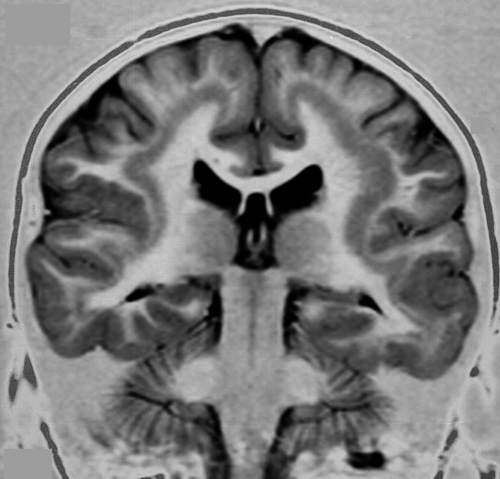

So, basically he suggests that it is better to avoid the use of the term “laminar” altogether, because even though subcortical “laminar” heterotopias may have some sort of laminar or layered appearance, they are less “banded” than the true band heterotopia and do occasionally degrade into a more nodular form. Below is a picture of a subcortical band heterotopia.

Image of a subcortical band heterotopia, borrowed from here.